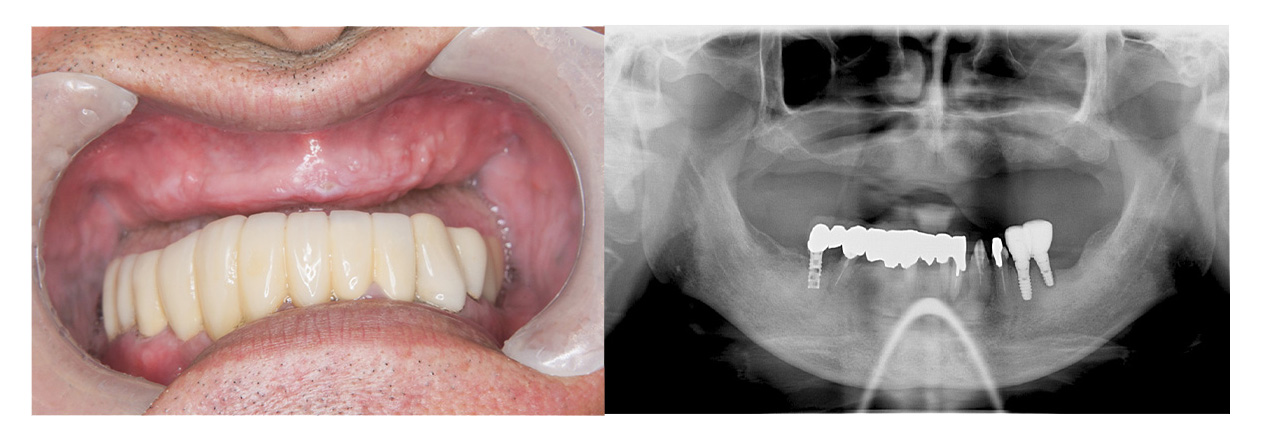

症例その2オールオン4 + ザイゴマ

• Before

• After

合わない総入れ歯と歯周病がひどい部分を全部除去してオールオン4とザイゴマにて治療した症例。